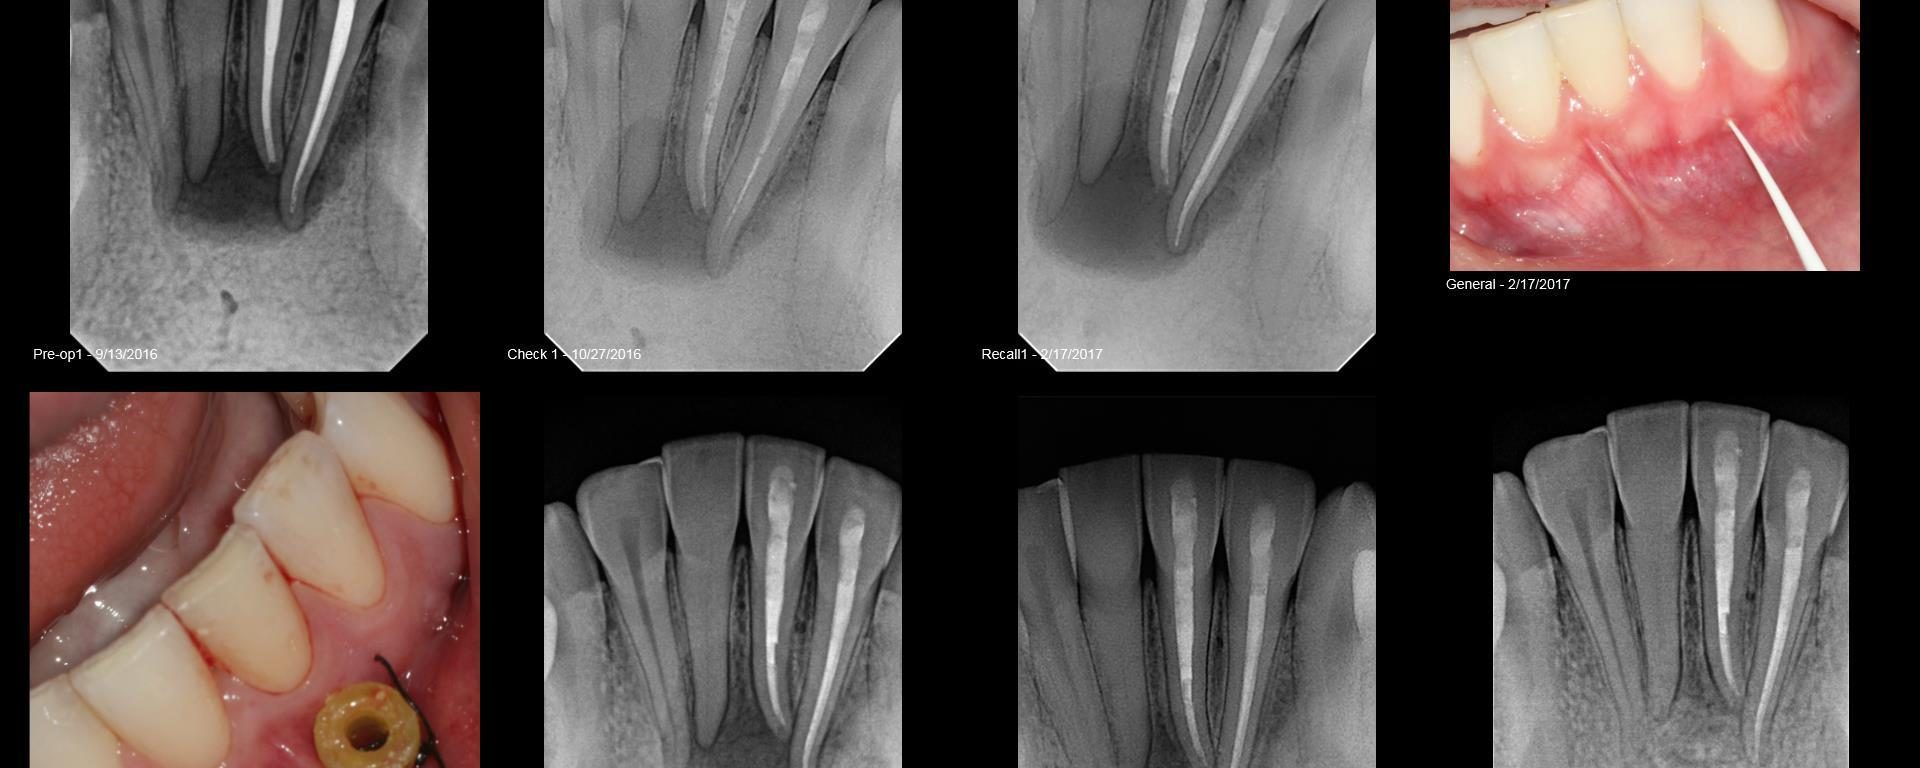

Apexogenesis

July 27, 2018 10 comments

Very young 7 yo male.  Original injury Nov 2015. Tooth was restored/bonded and became symptomatic 6 mo later.  He saw another endodontist who open the tooth with much difficulty due to patient behavior and uncooperative way. I took over the case, premedicate the pt with valium and eventually removed the old grey MTA because he remained […]